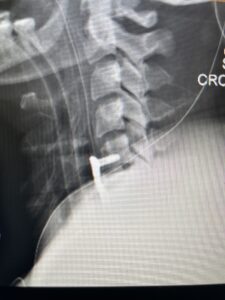

Fig. 3 Intraoperative lateral cervical X-Ray demonstrating C4-5 ACDF